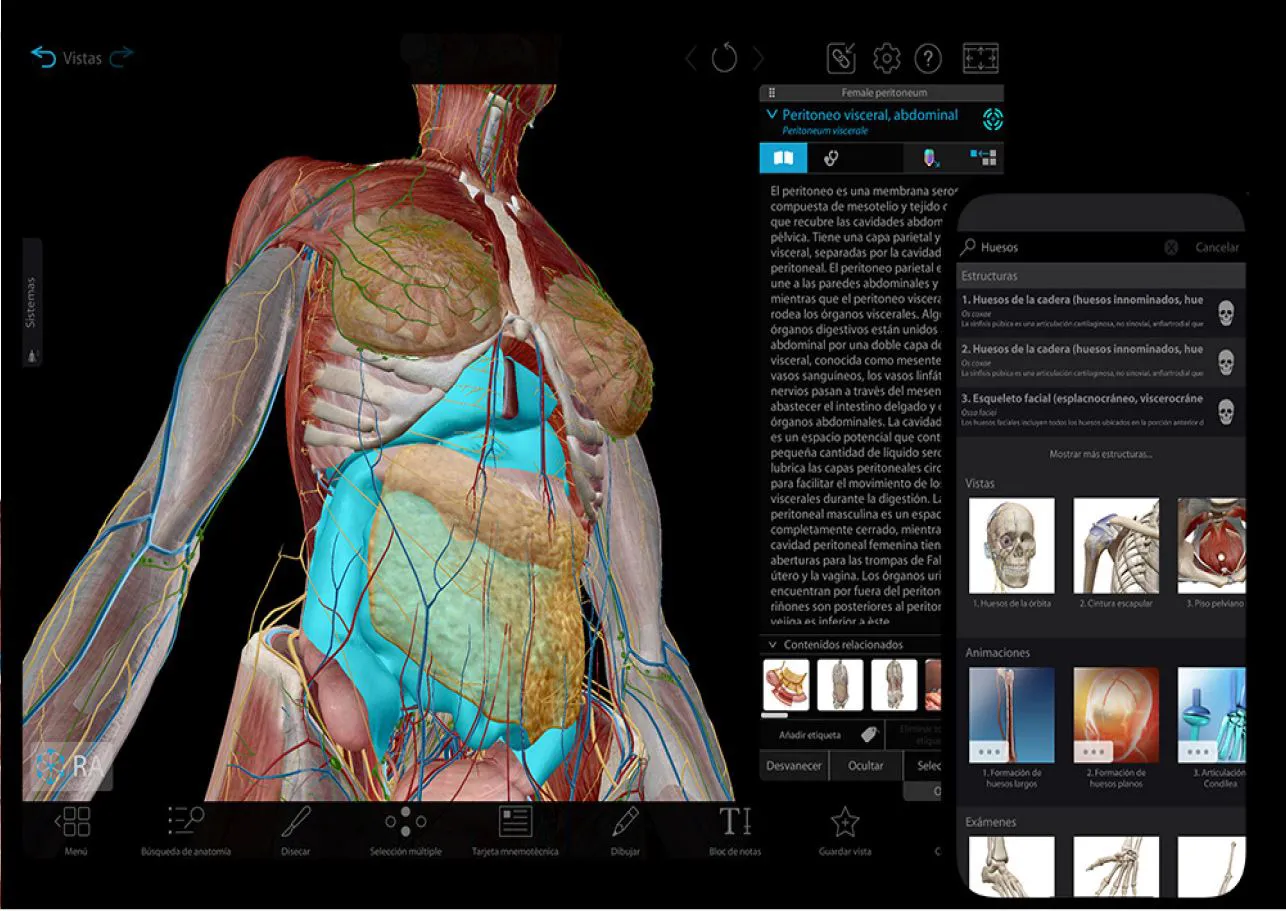

SIT Anatomy

La mesa SIT Anatomy es una solución versátil de alta tecnología con modelos 3D basados en cadáveres reales y renderizados foto realísticamente. Ofrece:

Exploración detallada de la anatomía humana y veterinaria

Herramientas interactivas de disección virtual

Estudio morfofuncional con correlación clínica